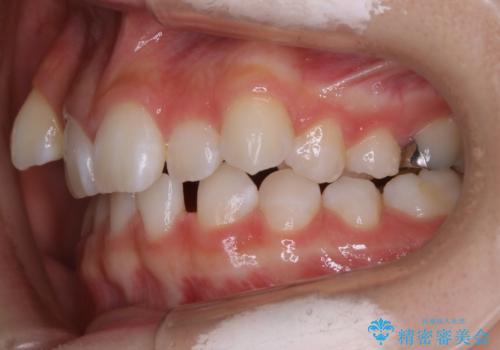

【抜歯】歯の先天欠如 歯の本数が上下で違う場合の治療

- 歯のガタつきを主訴にご来院されました。

ガタつきがあるだけでなく、元々永久歯が欠損している「先天欠如」で歯の本数が少なく噛み合わせ等も治療する必要がありました。

かなり特殊な状況からの矯正治療になるため抜歯する本数や位置、並んだあとのスペースのコントロールを慎重に計画し、マウスピース装置のインビザラインで治療を開始しました。